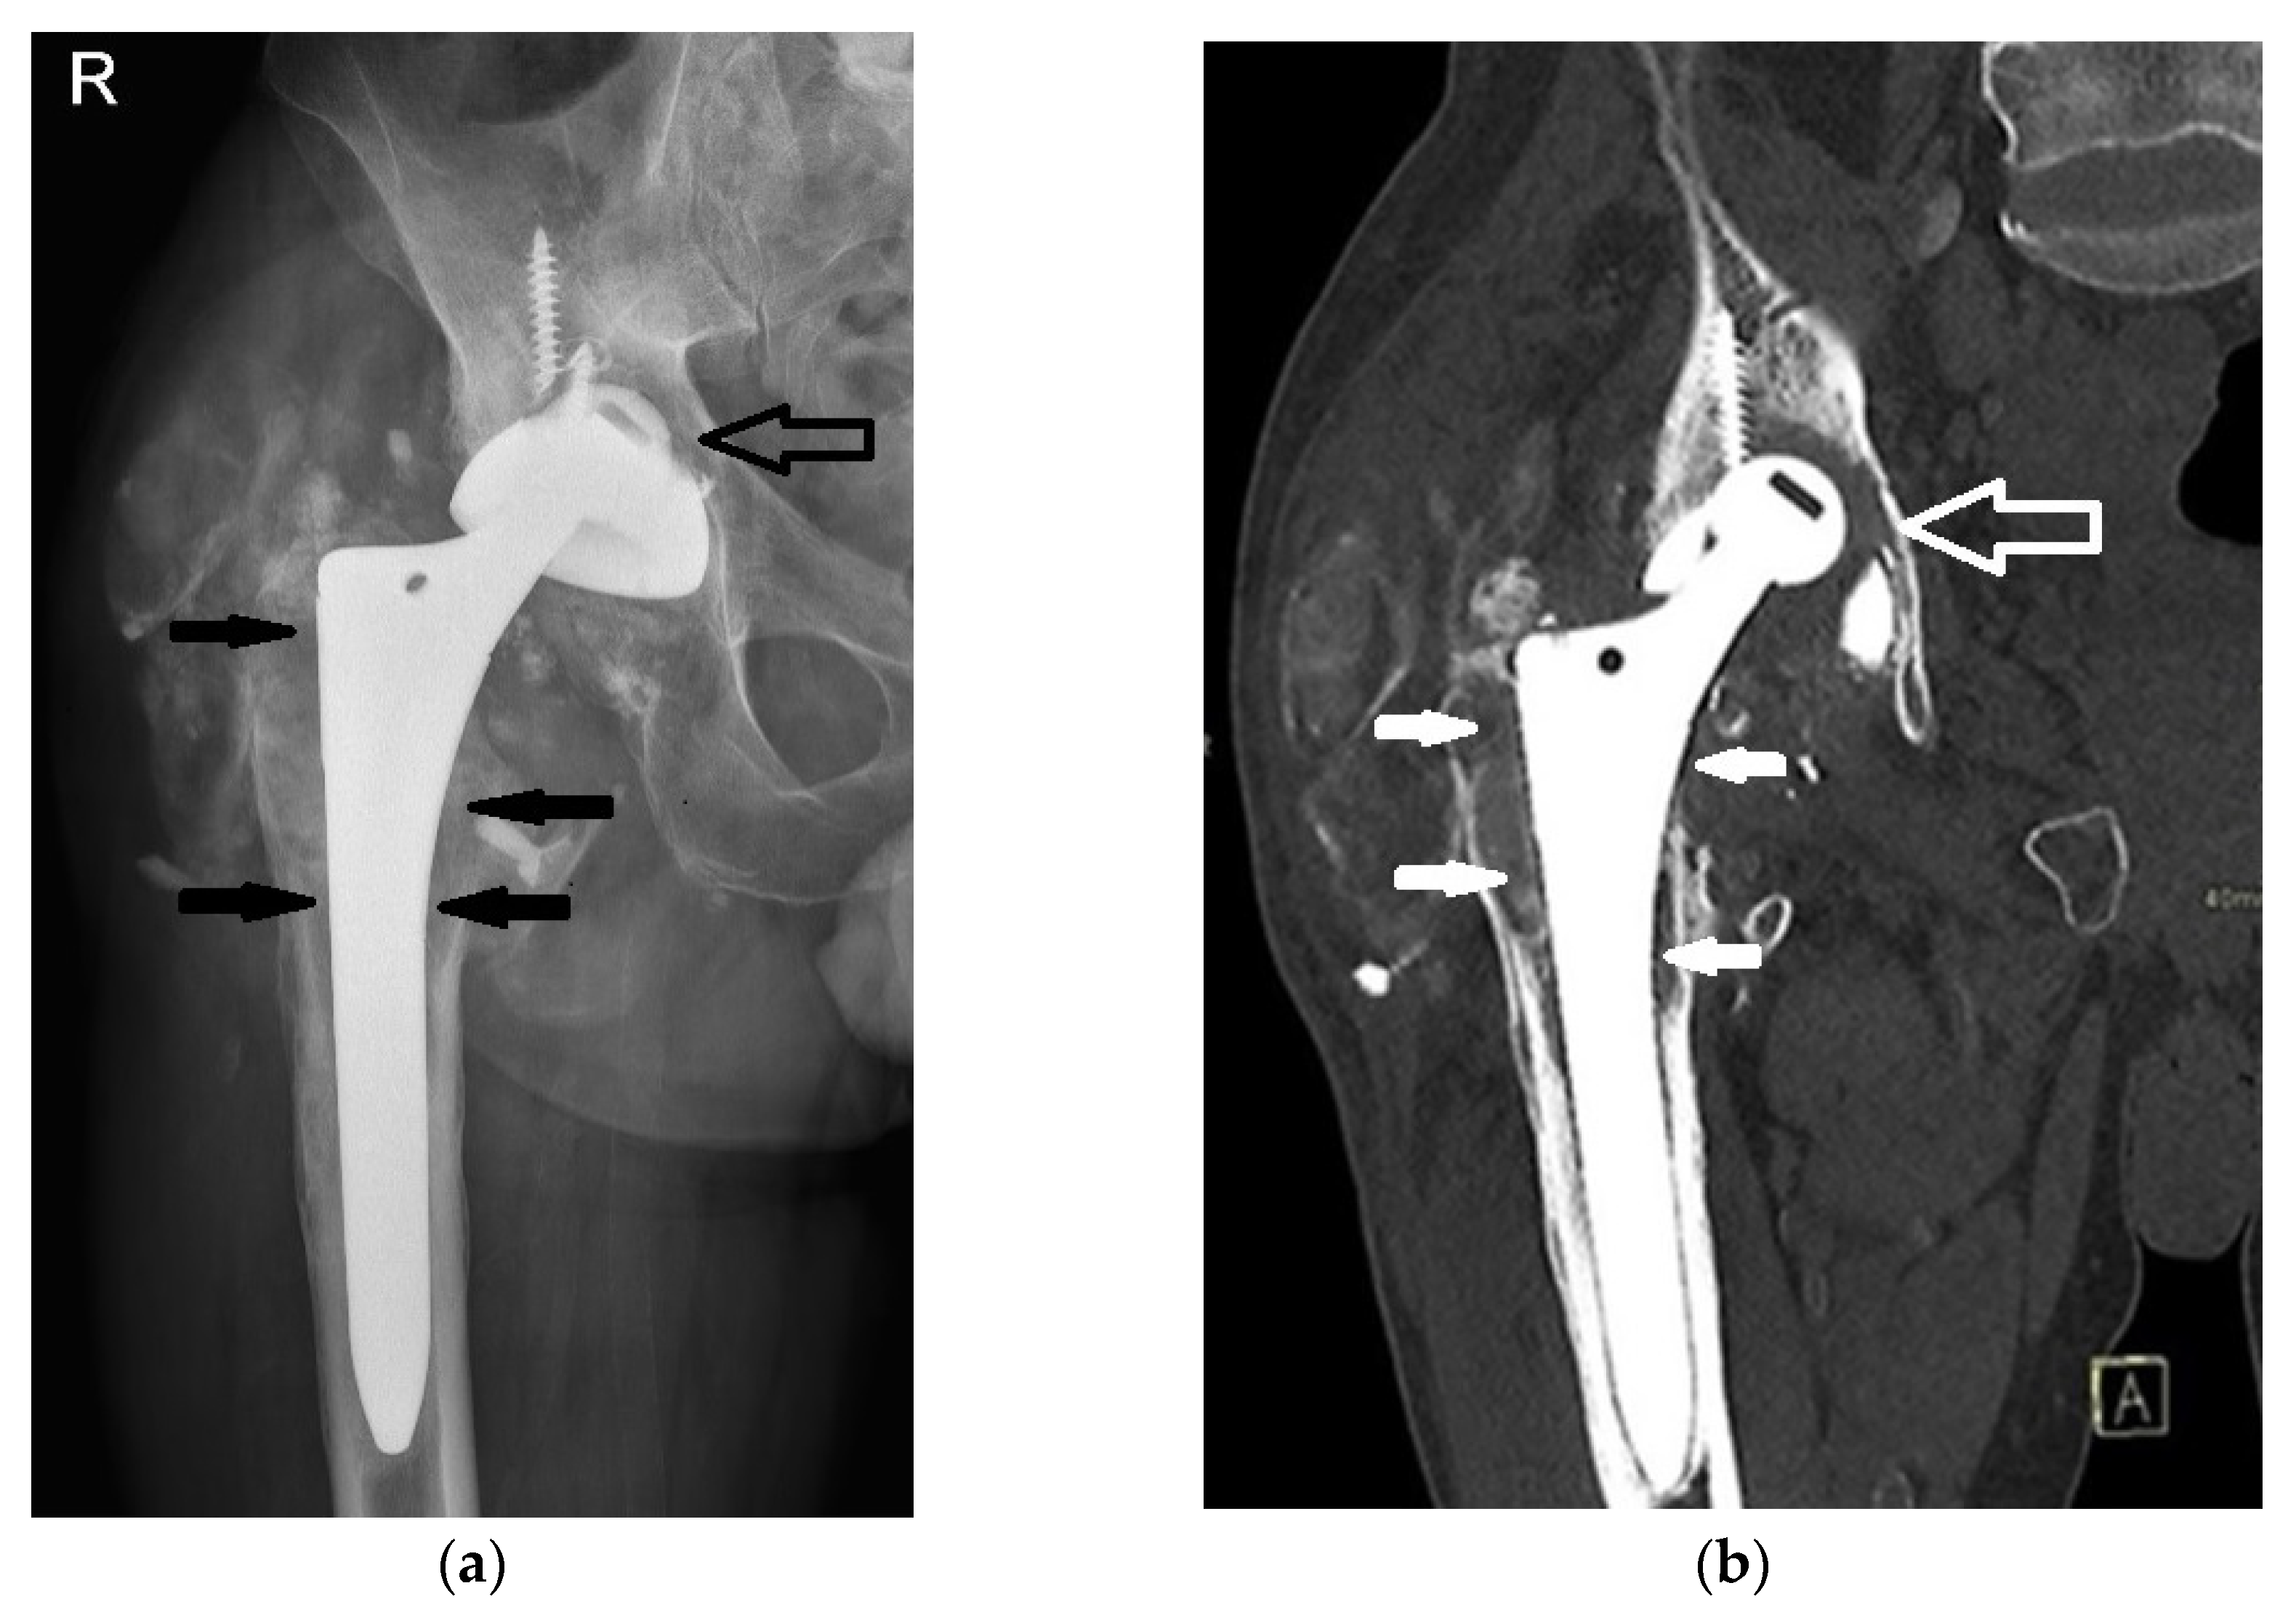

2. Case Presentation